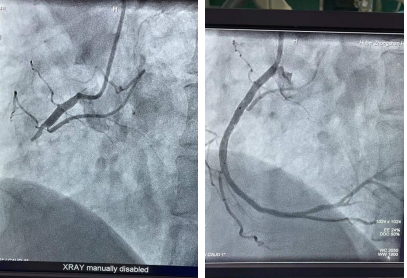

邹先生闭塞的血管(左)及开通后的血管影像(右)

经心电图提示,邹先生为ST段抬高型心肌梗死,这一次,邹先生没有半点犹豫,在医生的建议下接受急诊介入治疗。开通绿色通道后,心血管内科副主任李昌与副主任医师张明争分夺秒地为邹先生进行手术,术中邹先生突发室颤、心跳骤停,情况十分凶险,介入团队沉着应对,立即给予胸外心脏按压及电除颤,经过全力抢救,邹先生心跳恢复。手术结束后,邹先生被送入CCU病房,在医护人员精心治疗和护理下,邹先生恢复良好,术后第七天就康复出院了。